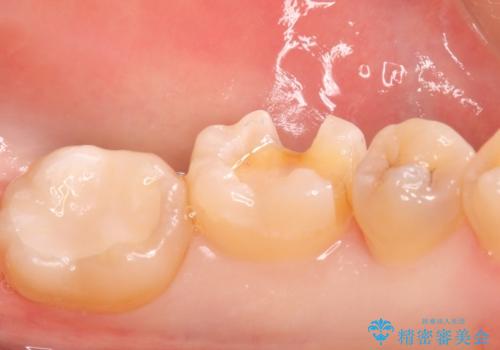

- メタルインレーをセラミックインレーに変えたいとの事で来院。

メタルインレーを外し、拡大鏡下でう蝕がないことを確認して

セラミックインレー(e-maxインレー)にて治療しました。

- e-maxインレー 7.7万円 費用は治療当時の料金となります